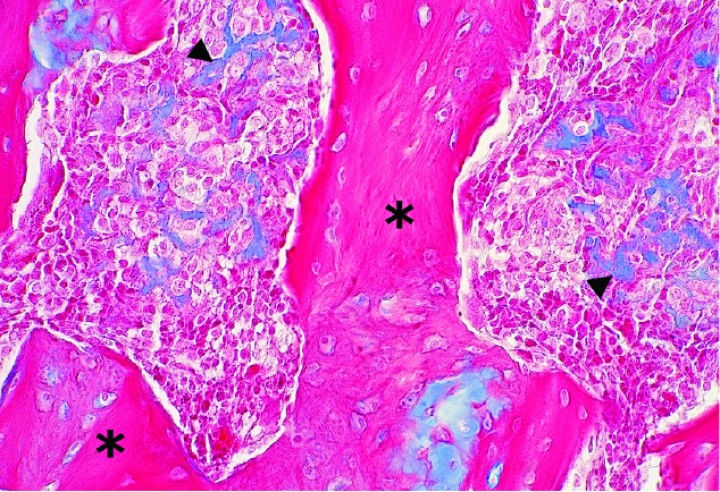

En las 4 cobayas evaluadas con azul alcián, la matriz extracelular se tiñó de color azul intenso con excepción de las zonas osificadas, que eran eosinófilas pálidas a rojas (Figs. 9-12). Las células mostraron un núcleo de redondo a elíptico o irregular con la cromatina laxa o granular, 0-3 nucléolos ocasionalmente prominentes y una cantidad media de citoplasma eosinófilo o basófilo pálido variablemente vacuolizado. La anisocitosis, anisocariosis, pleomorfismo y anaplasia eran generalmente moderados y se distinguían entre 0-3 mitosis por campo de 40 aumentos. En dos cobayas se apreció embolismo de células neoplásicas en vasos sanguíneos y en 3 casos se observaron focos de metástasis pulmonar (Fig. 12). Los niveles de sección evaluados de las múltiples masas de la extremidad posterior hasta zona lumbar de la cobaya 4 no revelaron tejido linfoide, motivo por el cual no se pudo demostrar de forma definitiva que alguna de ellas correspondiera a metástasis en linfonodos regionales. En algunos casos, la neoplasia mostraba amplias áreas de necrosis y/o hemorragia aguda, además de pequeños focos de hemosiderosis.

<p>Cobaya 2. Imagen microscópica de una zona de osificación endocondral prominente (asteriscos) de un condrosarcoma con depósitos no osificados de matriz cartilaginosa (cabezas de flecha). (Azul alcián, x480).</p>

Figura 11

Cobaya 2. Imagen microscópica de una zona de osificación endocondral prominente (asteriscos) de un condrosarcoma con depósitos no osificados de matriz cartilaginosa (cabezas de flecha). (Azul alcián, x480).